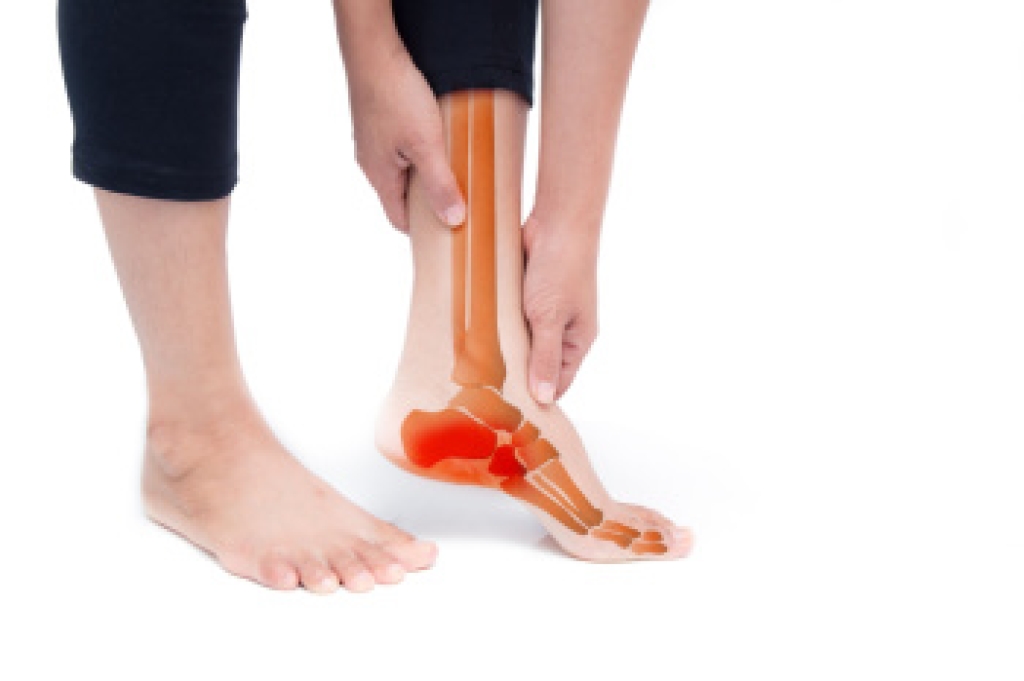

When the nerves in the feet lose sensation or do not send signals properly, the risk of injury increases. Cuts, blisters, or sores may go unnoticed and can become infected before they are detected. Reduced awareness of temperature can lead to burns from hot surfaces, or frostbite in cold conditions. Balance may be affected, making falls more likely. Over time, untreated injuries and infections can progress to serious tissue damage, sometimes requiring surgical intervention. Chronic pain from nerve damage can also interfere with daily activities, sleep, and overall quality of life. In people with diabetes, these complications are especially concerning, as slower healing can lead to further medical issues. Regular foot checks, wearing protective footwear, and prompt attention to any changes are essential steps in prevention. If you have symptoms of nerve damage, it is suggested that you see a podiatrist for a thorough evaluation and guided advice.

Neuropathy is a condition that leads to damage to the nerves in the body. Peripheral neuropathy, or neuropathy that affects your peripheral nervous system, usually occurs in the feet. Neuropathy can be triggered by a number of different causes. Such causes include diabetes, infections, cancers, disorders, and toxic substances.

Those with diabetes are at serious risk due to being unable to feel an ulcer on their feet. Diabetics usually also suffer from poor blood circulation. This can lead to the wound not healing, infections occurring, and the limb may have to be amputated.